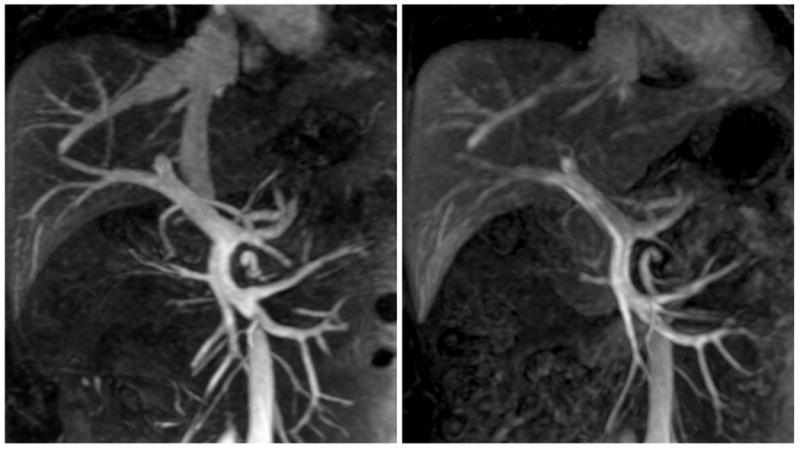

Figure 2 shows representative maximum intensity projections (MIPs) of the arterial phase MRA performed with FE4mg and undiluted GD with comparable image quality. Figure 3 shows an example of the venous phase of FE-enhanced MRA in one of the normal volunteers, compared to GD-enhanced MRA with an undiluted bolus. Note the greater CNR with ferumoxytol due to the long intravascular half-life. Figure 4 shows a case of a prominent right inferior phrenic artery imaged with FE2mg (left) and undiluted GD (right). Note the improved depiction of the origin of the vessel in the ferumoxytol-enhanced image due to less edge blurring. Figure 5 shows an example of multiple renal arteries originating in close proximity of each other imaged with FE4mg (left, relCNR 9.8) and diluted GD (right, relCNR 18.5) with equivalent image quality but higher relative CNR with GD.

Figure 5.

Case of multiple renal arteries originating in close proximity imaged with FE4mg (left, relCNR 9.8) and diluted GD (right, relCNR 18.5) with equivalent image quality but higher relCNR with GD (20 mm MIPs).